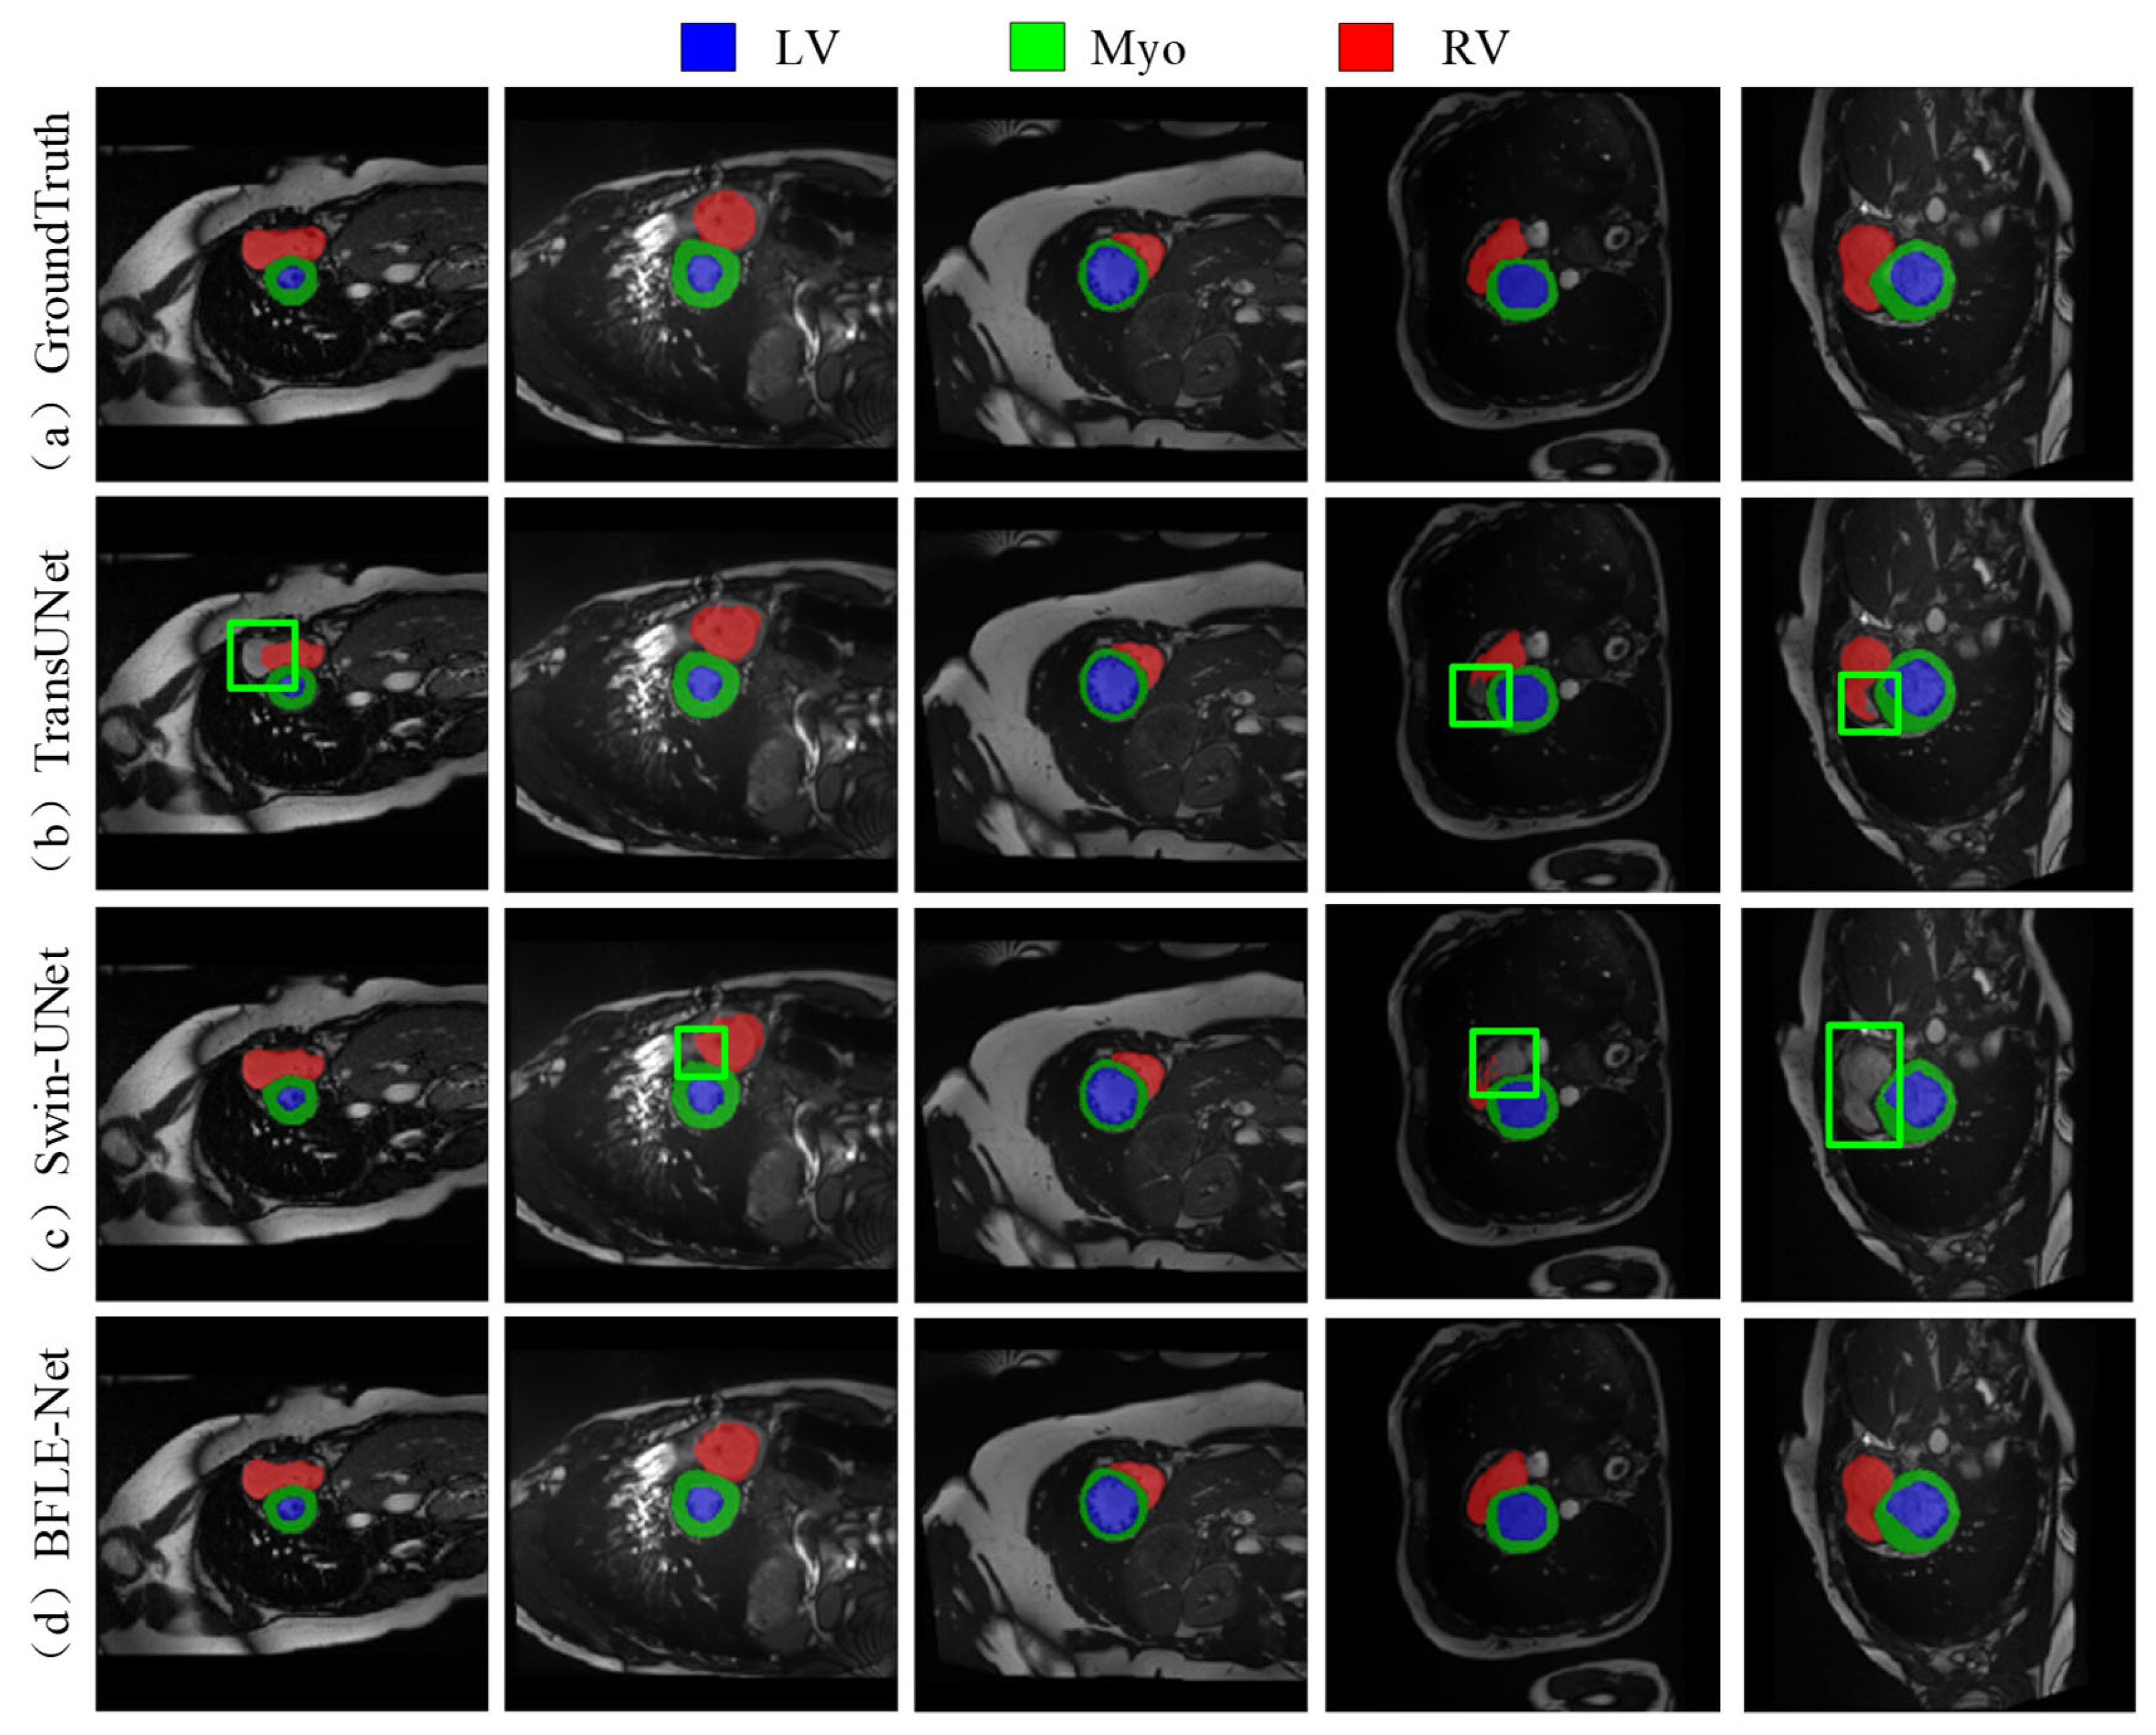

As shown in Figure 7, the existing methods also show obvious limitations in the right ventricle segmentation task in the ACDC dataset. Both TransUNet and Swin-UNet struggle with missing the right ventricle structure. By adopting a dynamic feature calibration mechanism, the method in this study completely preserves the fine anatomical structural features of the right ventricle and significantly optimizes boundary continuity.

Figure 7. Qualitative analysis results on the ACDC dataset. Note: The green box in the figure indicates the location where the effect of segmentation is insufficient.

Electronics 14 03054 g007